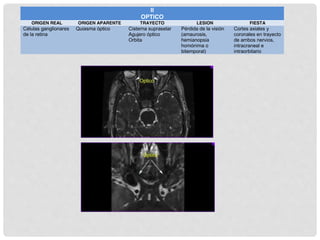

II ÓPTICO

NERVIO ÓPTICO

Se traduce en señal

eléctrica en los conos y

bastones

Pasa a las células

bipolares que son las

neuronas sensoriales

primarias

De ahí pasa a las células

ganglionares que son las

secundarias

Los axones de

las c

ganglionares

convergen en el

NO

NO DEJA

LA ÓRBITA

POR EL

CANAL

ÓPTICO

SE UNE AL

DEL OTRO

LADO Y

FORMA EL

QUIASMA

LA MITAD

DE LOS

AXONES

CRIZAN LA

LÍNEA

MEDIA

CGL

TRACTO

G.C

(RADIACI

ONES

ÓPTICAS)

CORTEZA

VISUAL

PRIMARIA